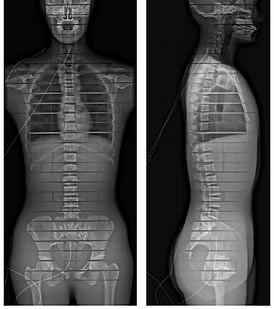

脊柱側彎

EOS 低輻射劑量 X 光檢查掃描,

提供身體全面分析